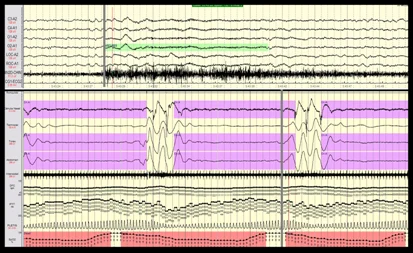

En los casos con sospecha de  epilepsia o cuando se quiere una monitorización más amplia de la actividad cerebral cortical durante el sueño, el registro de PSG con EEG nos permite valorar más tiempo de registro que un electroencefalograma convencional debido a  que el sueño puede ser un inductor de la actividad epiléptica  en algunos casos de epilepsia.

Los microdespertares durante el sueño   nos informa sobre fragmentación sueño, eventos s muy importante para valorar la calidad del sueño. Estos  se definen un aumento de la frecuencia de la actividad cerebral de base durante el sueño, de una duración de 3 a 15 segundos, acompañada o no de un aumento de la actividad de EMG, aunque en el sueño REM este último criterio es obligado. Estos eventos deben tener 10 segundos de sueño antes y después del evento.

• Actividad cerebral mediante electroencefalografía (EEG),

• Actividad muscular mediante electromiografía (EMG) del mentón y de las extremidades inferiores

• Actividad del movimiento ocular mediante electrooculograma (EOG)

Estos parámetros nos permiten realizar un minucioso análisis de la estructura del sueño de cada paciente valorando  los diferentes porcentajes de las distintas  fases de sueño (fase 1, fase 2, fase 3 y REM), el número de ciclos, la latencia de sueño, la latencia de sueño REM, la eficiencia de sueño entre otros.

La codificación de las distintas fases de sueño se realiza de la siguiente manera:

• La fase 1 del NREM es la transición desde la vigilia al sueño con movimientos oculares lentos.

• La fase 2 del NREM se define por la aparición de complejos K , en este caso la actividad ocular permanece ausente y el EMG continúa de manera similar al estadio 1. Las fase 1 y  2 se les  conoce como sueño lento superficial.

• La fase 3 del NREM, también llamado sueño lento profundo,  se caracteriza por ser un sueño con más del 20% (pero menos del 50%) de actividad delta de amplitud elevada Los husos del sueño pueden persistir, sigue sin haber actividad ocular, y la actividad del EMG permanece a un nivel disminuido.

• El sueño REM se caracteriza por un EEG de baja amplitud y de frecuencia mixta similar al de la fase 1 del NREM. El EOG muestras  movimientos oculares rápidos, similares a las que se observan cuando estamos  despiertos y con los ojos abiertos. La actividad del EMG  refleja  atonía muscular completa muy  característica de este estado.